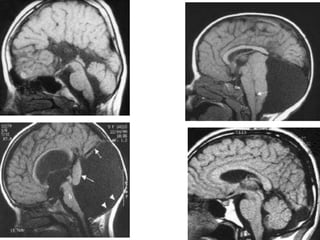

Ressonância magnética

• 4º ventrículo aberto para um largo cisto de

fossa posterior;

• Alta inserção da tenda do cerebelo;

• Pequeno e displásico vermix cerebelar

Ressonância magnética •4º ventrículo aberto para um largo cisto de fossa posterior; • Alta inserção da tenda do cerebelo; • Pequeno e displásico vermix cerebelar